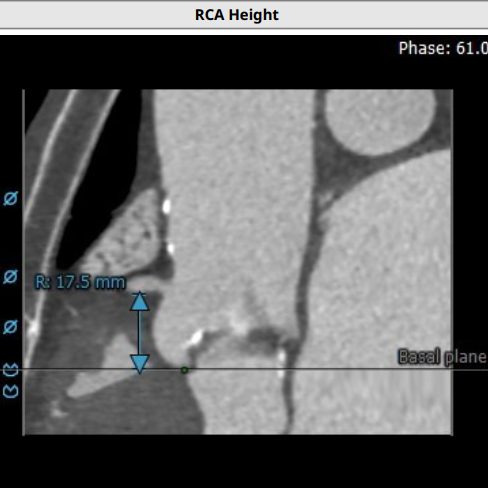

超声心动图显示,主动脉最大流速482cm/s,最大压差93mmHg,平均压差50mmHg,LVEF65%。CT显示主动脉瓣为TYPE2型二叶瓣,严重钙化,右无、左无可见粘连伴钙化,瓣环平面可见钙化,钙化延伸至流出道及二尖瓣前叶根部,左冠高度约12mm,瓣叶长度14.9mm,存在一定左冠风险,法式窦平均直径33.7mm,STJ高度约21.8mm、直径约30.2mm。

主动脉弓部走行较平缓,弓顶部可见少许钙化,主动脉弓部三根毛开口未见明显狭窄征象、未见发育变异,胸主动脉、腹主动脉走行较平直、腹主动脉多发严重钙化斑块,管腔未见明显狭窄,双侧髂动脉-股动脉走形迂曲,双侧髂动脉多发严重钙化斑块,部分呈半环形、马蹄形分布,右侧股动脉可尝试做为主入路,左股动脉作为脑保护入路。虚拟瓣环直径25mm,左室流出道平均直径23.3mm,拟植入VenusA Plus 23/26号的瓣膜。术中balloon sizing确认瓣膜型号,同时确认冠脉风险。